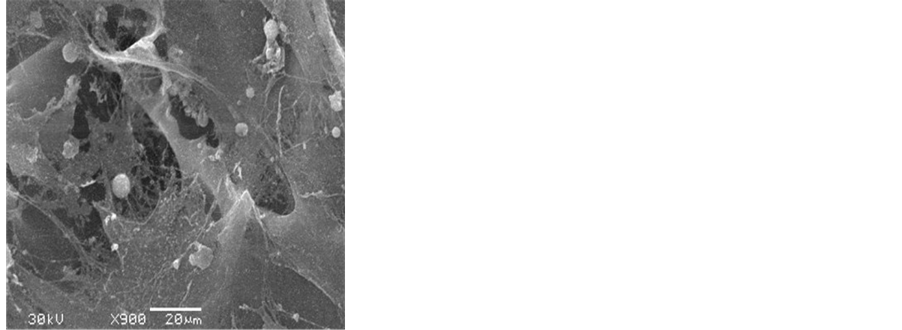

4.1. SEM Observation of the Silk Fibroin Scaffold before and after Adipogenic Induction

The silk fibroin scaffold possesses a natural porus 3D spatial structure, the aperture is uniform in the internal scaffold, and interconnected each other, the aperture is 50 - 60 μm, the porosity is up to 90% (Figure 1). After adipogenic induction culture for 2 weeks, the hUCMSCs differentiated into rounded adipocytes and a lot of extracellular matrix secreted.

Figure 1. Silk fibroin scaffold under SEM, before and after coculture with hUCMSCs. (a) Silk fibroin scaffold (SEM, ×200); (b) Cell-scaffold complex, 2 weeks after adipogenic induction (SEM, ×900).

4.3. The Result of Coculture of hUCMSCs with Silk Fibroin Scaffold

The hUCMSCs showed rounded adipogenic cells under SEM, after adipogenic culture in silk fibroin scaffold in insulin-IRES-EGFP gene transfection group (A) and EGFP gene transfection (group B), secreting a lot of extracellular matrix and covering the scaffold material completely (Figure 3) under the fluorescent inverted phase- contrast microscope. After Oil Red O staining, a lot of adipocytes appeared in silk fibroin scaffold, round adipose droplets showed intracellularly, the size of the adipocytes was not homogenous; the density of adipocytes in group A are much more higher than that in group B, be equal to the (1.6 ± 0.2) times of group B (Figure 4, Figure 5). The difference of the cell density between the two groups was significant (P = 0.007, P < 0.01).

Scaffold is the key factor in the construction of tissue engineering tissues. In this study, we chosed silk fibroin as the scaffold, it possesses a good property of mechanic and biocombatibility, biodegradation, rich source and very cheap. Hofmann’s experiment revealed that silk fibroin could not only combine with MSCs in vitro, but also adhere to the preadipocytes and maintain the shape of preadipocytes [26] . On the immunogenicity, Wang [27] reported that during the whole implantation period, all the scaffold showed a good compatibility, the reaction between the animal and the grafts was minimal. Our previous study revealed that an aperture of 50μm of the silk fibroin was of choice in the construction of tissue engineering adipose [28] . Under SEM, the silk fibroin scaffold possesses natural porous 3D spatial structure, the aperture is uniform in the internal scaffold, interconnecting with each other, an aperture of 50 - 60 μm, a porosity of 90%, hUCMSCs adhered to the scaffold tightly, grew well, and secreted extracellular matrix. The result of the experiment showed that the scaffold was good for the cell growth. The activity of hUCMSCs in silk fibroin sccaffold after gene transfection by MTT test showed that the difference of the absorbance in cell group and in cell scaffold group, was not significant (P = 0.066, P > 0.05). These results revealed that the silk fibroin scaffold was not toxic to the growth and proliferation of hUCMSCs after gene transfection.